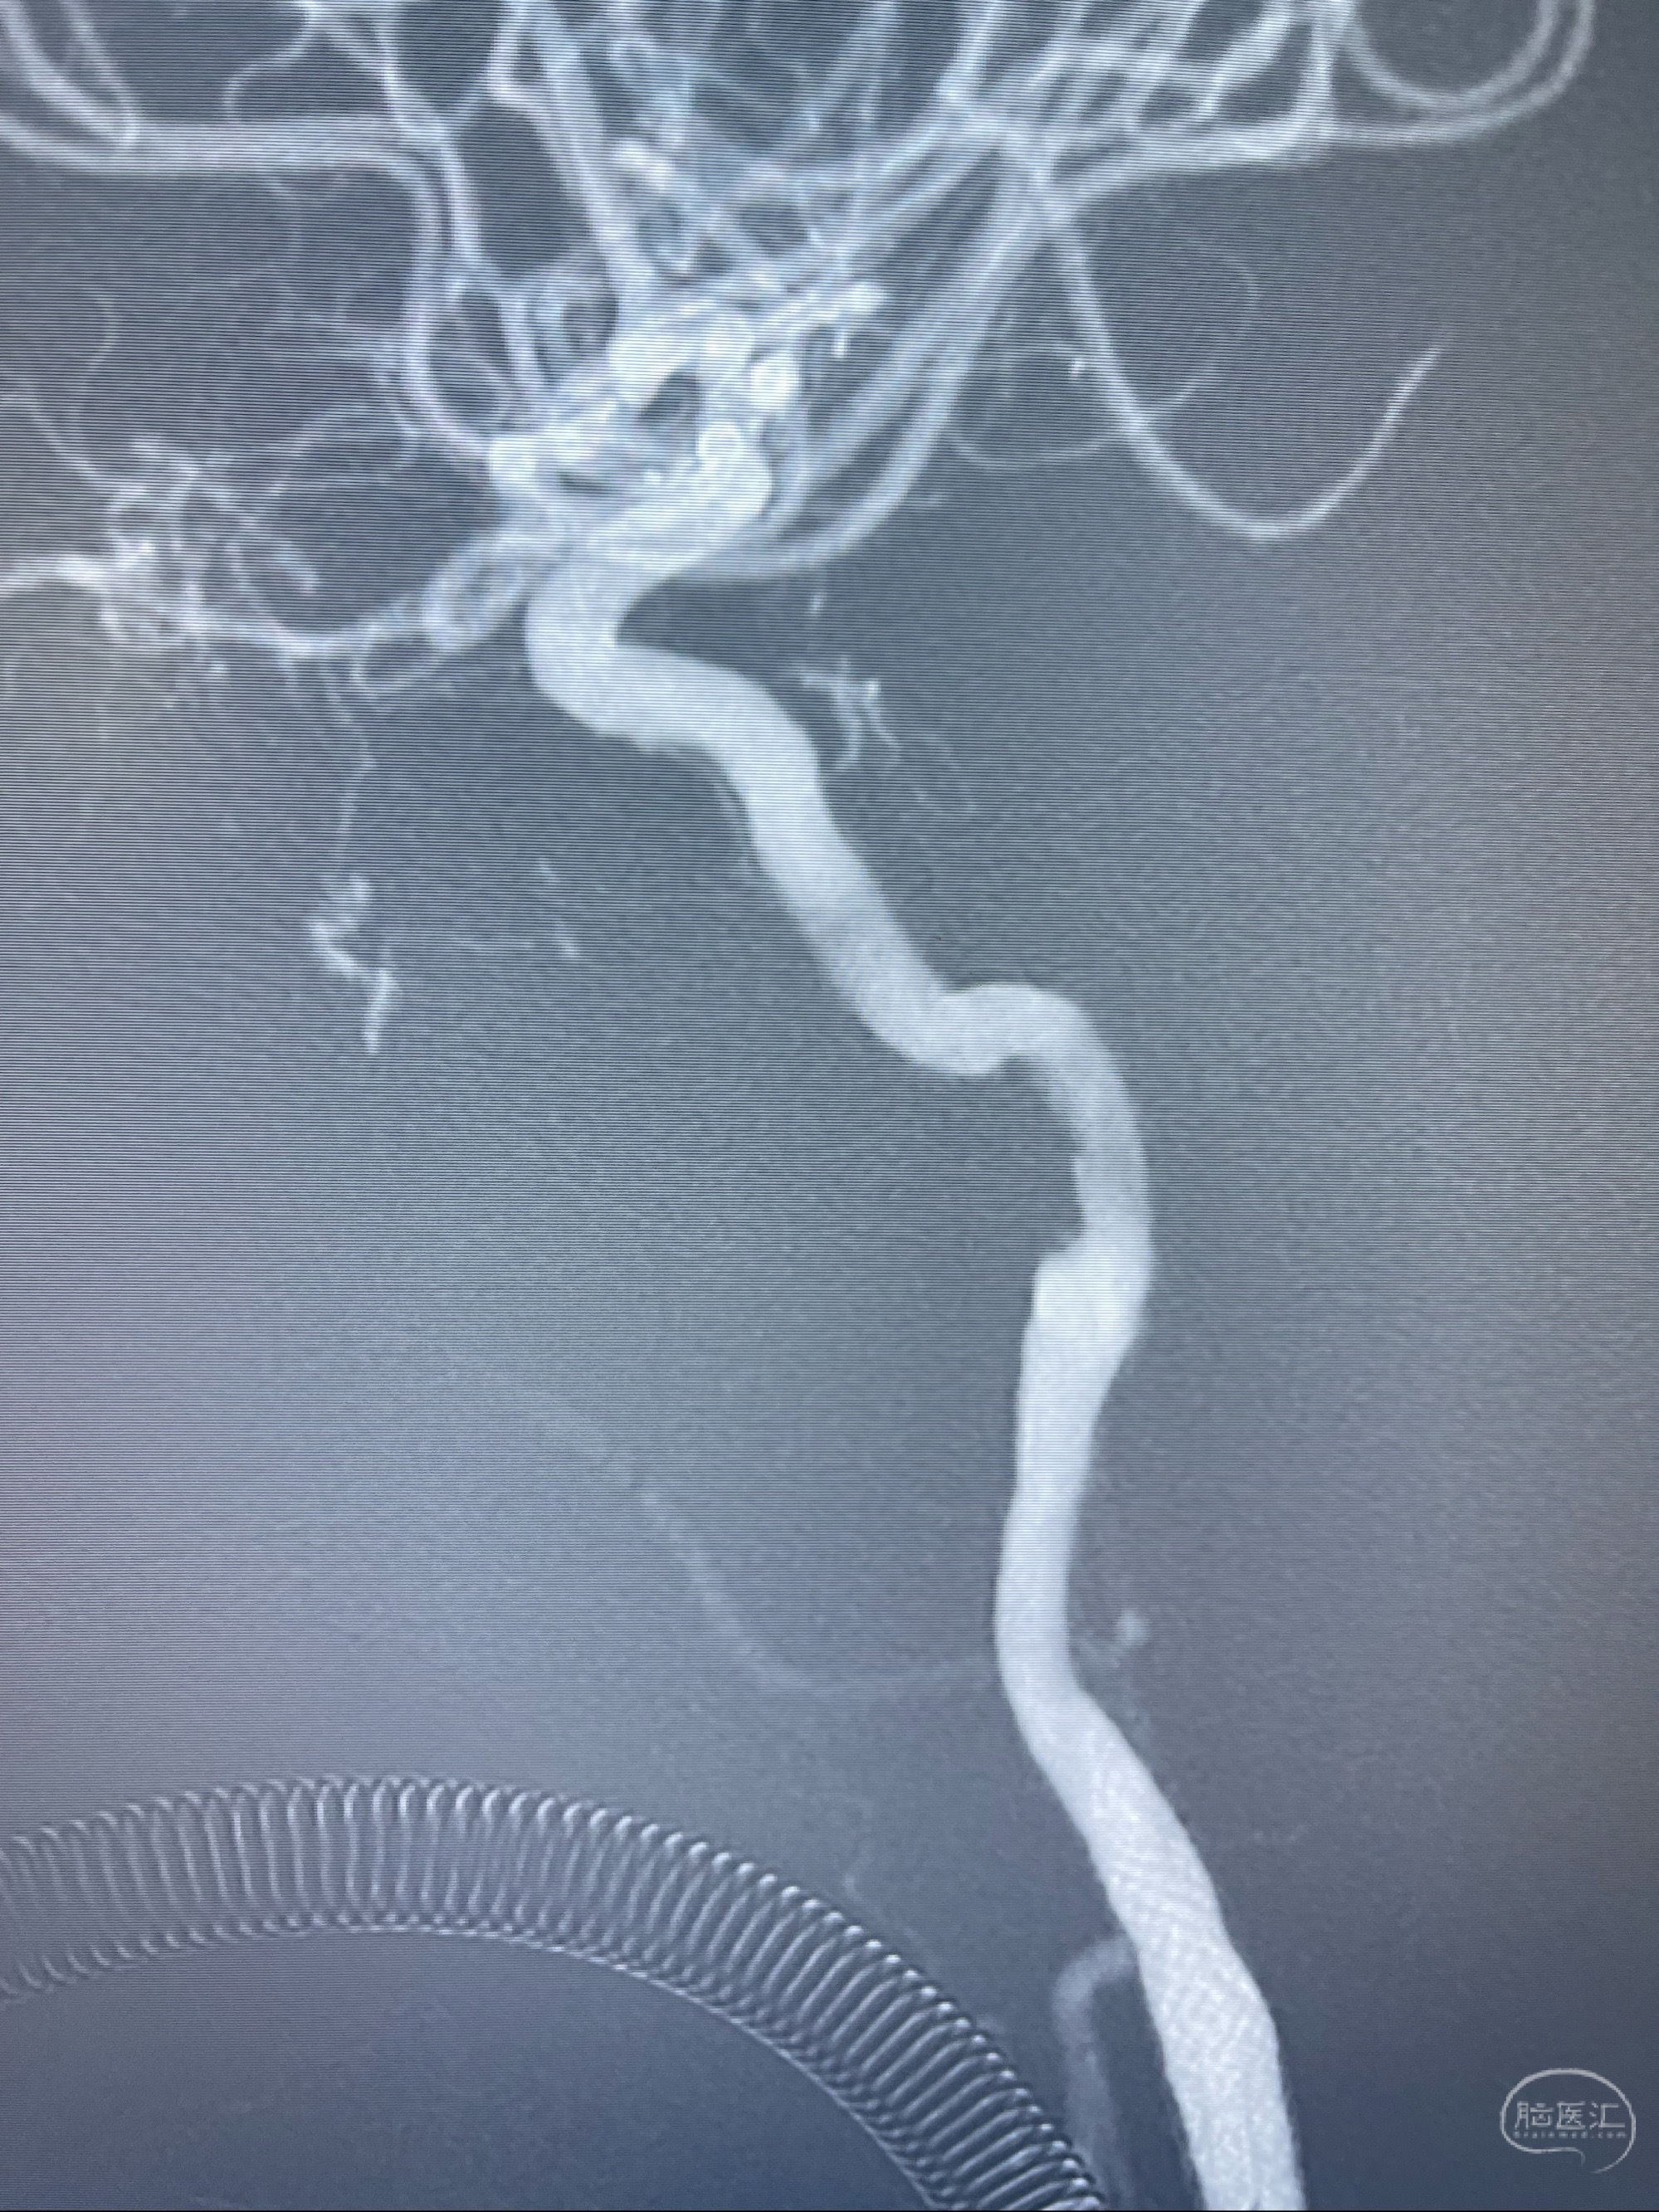

泄除球囊造影显示局部管腔扩张佳

后移球囊至颈段狭窄段,以8-12个大气压扩张,持续30s后泄除球囊

即刻造影显示狭窄扩张佳

重新行“路径图”,支架导管在微导丝引导下超选择性插入至右侧颈内动脉眼段,4.5-50mmLeo支架释放,远心端位于海绵窦段,近心端位于岩骨段狭窄段以近

即刻造影显示支架贴壁佳